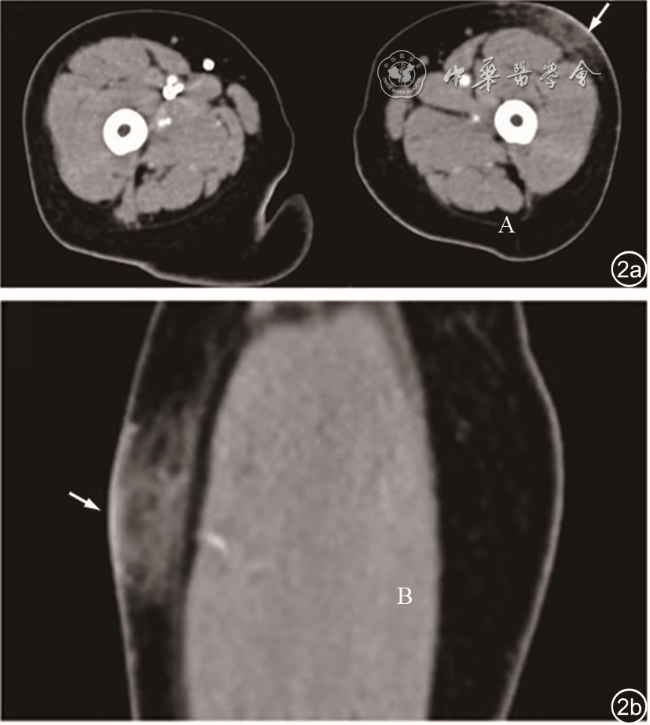

图1 左大腿包块超声图像。图a为常规二维超声示皮下脂肪层内稍高回声区(箭头所示);图b为彩色多普勒血流成像示其内血流信号不明显(箭头所示)